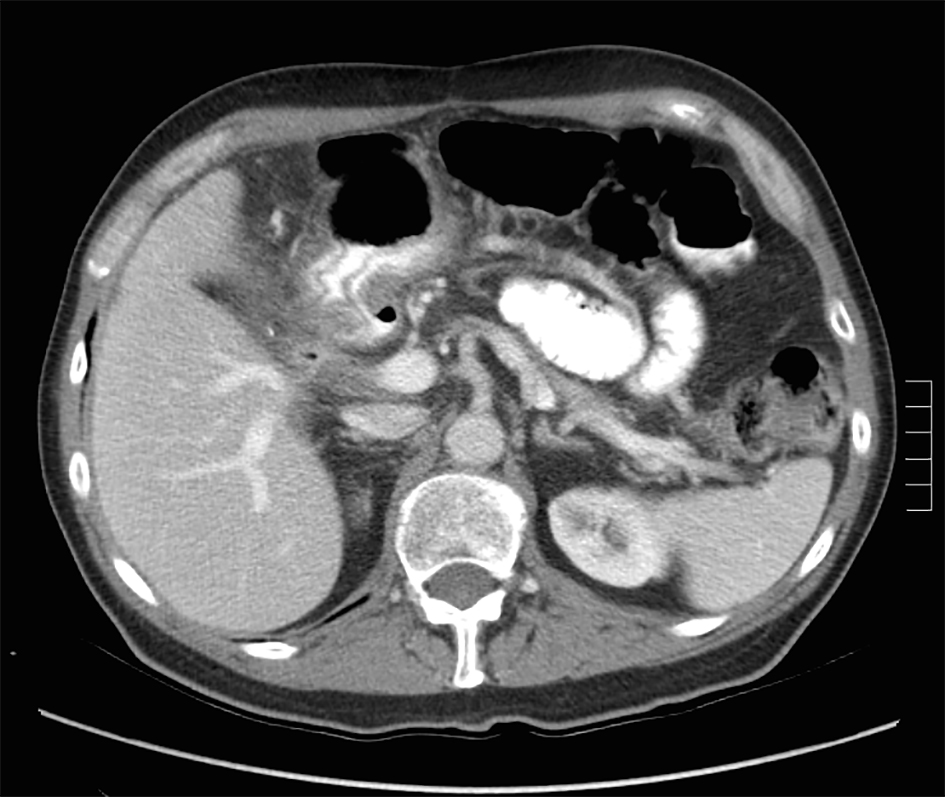

Pancreatic Cancer Ct Scan - Pancreatic cancer, CT scan - Stock Image - C037/8292 ... - Pancreatic cancer will typically refer to ductal carcinoma of the pancreas, which comprises up to 90% of primary pancreatic malignancies.

Pancreatic Cancer Ct Scan - Pancreatic cancer, CT scan - Stock Image - C037/8292 ... - Pancreatic cancer will typically refer to ductal carcinoma of the pancreas, which comprises up to 90% of primary pancreatic malignancies.. The abdominal ct scan may show problems with the gallbladder, liver, or pancreas, including Pancreatic cancer (cancer of the pancreas) mainly occurs in people aged over 60. A ct scan is one of the most common tests for pancreatic cancer. A pet scan is often done in combination with a ct scan. Why aren't pancreatic ct scans used in routine physical examinations to detect and prevent the spread of pancreatic cancer?

A ct scan is often used as the primary test to diagnose or confirm pancreatic cancer. Effectiveness of ct scan for pancreatic cancer detection. Ct scans create pictures of your pancreas, gallbladder, and bile ducts. Learn how this test works, as well as its benefits and risks. Many cancer centers use a special ct scan method called a pancreatic protocol ct scan.

Before the scan, dye is injected into a vein to help make the pictures clearer. Ct scans help doctors diagnose and treat medical conditions such as pancreatic cancer. Ct scans are usually done at a hospital or a radiology clinic. This method focuses on taking pictures of the pancreas at specific. From my experience as the patient being diagnosed…. Ct scans can show pancreatitis or pancreatic cancer. Learn how this test works, as well as its benefits and risks. How do ct scans work? Contrast is a special dye used to make it easier. Ct scans are often performed to monitor patients after treatment to determine whether the cancer has recurred, changed in size or metastasized this test is not as specific as ct scanning and is not used alone to diagnose pancreatic cancer. A contrast dye injected at the start of the here are some other challenges to finding pancreatic cancer early: A ct scan is often used as the primary test to diagnose or confirm pancreatic cancer. Doctors commonly order ct scans if they think a person may have pancreatic cancer.

Ct scans can also be used to guide a biopsy needle into a suspected pancreatic tumor. Learn how this test works, as well as its benefits and risks. Ct scanning will visualize the vast majority of pancreatic cancers, and it provides important information to guide treatment. Many cancer centers use a special ct scan method called a pancreatic protocol ct scan. Why aren't pancreatic ct scans used in routine physical examinations to detect and prevent the spread of pancreatic cancer?

This provides a series of images from many different angles. Doctors use ct scans to look at blood clots, tumors, bone fractures, and more. Abdominal ct scan can provide a more detailed analysis of the pancreas and other abdominal organs and is much more accurate than ultrasound in detecting pancreatic cancer, with a sensitivity of about 90%. A ct scan can be helpful both for characterizing the tumor (determining its size and location in the pancreas) and looking for any evidence of spread to lymph nodes or other. Pet/ct fusion scan enhances ct staging in patients with pancreatic. Effectiveness of ct scan for pancreatic cancer detection. Ct scans are usually done at a hospital or a radiology clinic. Ct scanning will visualize the vast majority of pancreatic cancers, and it provides important information to guide treatment.

This depends on the reason for your ct scan and which part of your body your doctor needs to see. A contrast dye injected at the start of the here are some other challenges to finding pancreatic cancer early: Pancreatic cancer — overview covers symptoms, risk factors, prevention, diagnosis, surgery, chemotherapy and other treatment for cancer of several types of growths can occur in the pancreas, including cancerous and noncancerous tumors. A precontrast scan of the pancreas can be performed to look for calcifications within the pancreas, which may indicate the presence of a focal pancreatitis. A ct scan is often used as the primary test to diagnose or confirm pancreatic cancer. Effectiveness of ct scan for pancreatic cancer detection. A computerised tomography (ct) scan is a commonly used test to assess pancreatic cancer. Abdominal ct scan can provide a more detailed analysis of the pancreas and other abdominal organs and is much more accurate than ultrasound in detecting pancreatic cancer, with a sensitivity of about 90%. Ct scans are usually done at a hospital or a radiology clinic. Why aren't pancreatic ct scans used in routine physical examinations to detect and prevent the spread of pancreatic cancer? Ct scans can show pancreatitis or pancreatic cancer. Multidetector ct scanning (mdct) using a pancreas protocol is at least as accurate as eus in the overall determination of the resectability of pancreatic algorithm for evaluation of a patient with suspected pancreatic cancer. Contrast is a special dye used to make it easier.

Pancreatic cancer — overview covers symptoms, risk factors, prevention, diagnosis, surgery, chemotherapy and other treatment for cancer of several types of growths can occur in the pancreas, including cancerous and noncancerous tumors. A ct scan can be helpful both for characterizing the tumor (determining its size and location in the pancreas) and looking for any evidence of spread to lymph nodes or other. For evaluating possible pancreatic cancer, a multiphase helical ct scan or pancreatic protocol ct scan is often recommended. Pancreatic cancer versus chronic pancreatitis: Ct scans are usually done at a hospital or a radiology clinic.

This provides a series of images from many different angles. It takes pictures from different angles. Many cancer centers use a special ct scan method called a pancreatic protocol ct scan. Pancreatic cancer (cancer of the pancreas) mainly occurs in people aged over 60. Ct scans can also be used to guide a biopsy needle into a suspected pancreatic tumor. Ct scanning will visualize the vast majority of pancreatic cancers, and it provides important information to guide treatment. The ct scans, four of them over the course of the 11 weeks from my initial appointment with my primary (23 march). A ct scan is one of the most common tests for pancreatic cancer. It can show the pancreas it also helps doctors know how extensively cancer has spread in the pancreas. How do ct scans work? The most common type of cancer that forms in the. The abdominal ct scan may show problems with the gallbladder, liver, or pancreas, including For evaluating possible pancreatic cancer, a multiphase helical ct scan or pancreatic protocol ct scan is often recommended.